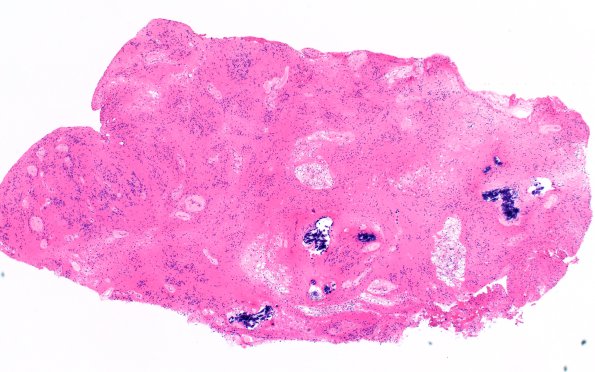

Washington University Experience | NEOPLASMS (GLIAL) | Subependymoma | 18B2 Subependymoma (Case 18) H&E 4X 2

H&E-stained sections show a neoplasm composed of clusters of monomorphic nuclei in a dense glial fibrillary background. There are scattered calcifications and areas of large foamy cells. (H&E)